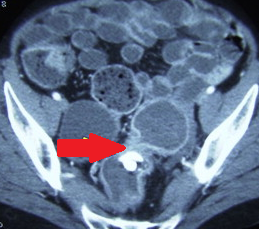

CT scan κοιλίας. Παρουσία ασβεστώσεων, κυστικο-συμπαγών περιοχών και λιπώδους ιστού, ενδεικτικά τερατώματος δεξιάς πλευράς (Ευγενική παραχώρηση Dr. V. Penopoulos)